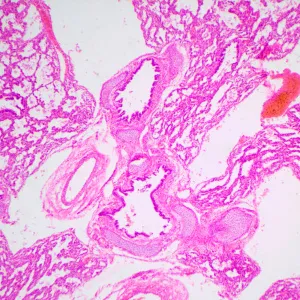

MAGUS Bio 240T – небольшой биологический микроскоп для студенческих занятий и исследований. Ориентирован на работу с прозрачными и полупрозрачными препаратами биологического происхождения в светлом поле. Микроскоп отличается наличием кодированного револьвера, который поддерживает выбранную интенсивность света для каждого объектива, и ЖК-дисплея, на котором отображаются параметры работы.

• Работает с прозрачными и полупрозрачными биологическими препаратами в светлом поле